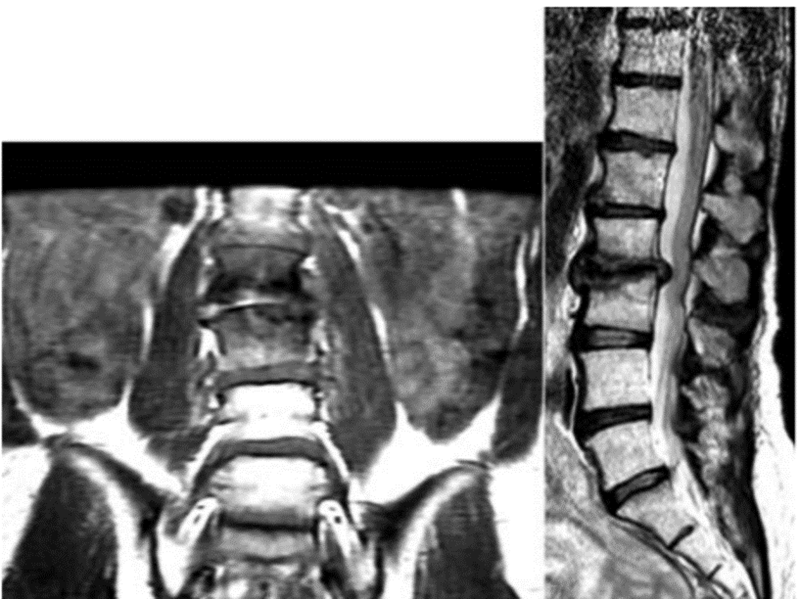

焦磷酸钙沉积疾病引起腰椎双侧症状性滑膜囊肿

CT扫描显示右侧与L4-L5关节突关节相关的钙化滑膜囊肿,明显侵犯椎管

A、注射钆前轴位T1加权MRI扫描显示硬膜囊背侧有低信号钙化肿块移位;B、注射钆后,低信号区周围可见强化环;C、矢状位T2加权MRI图像。箭头显示侧隐窝内有囊性肿块